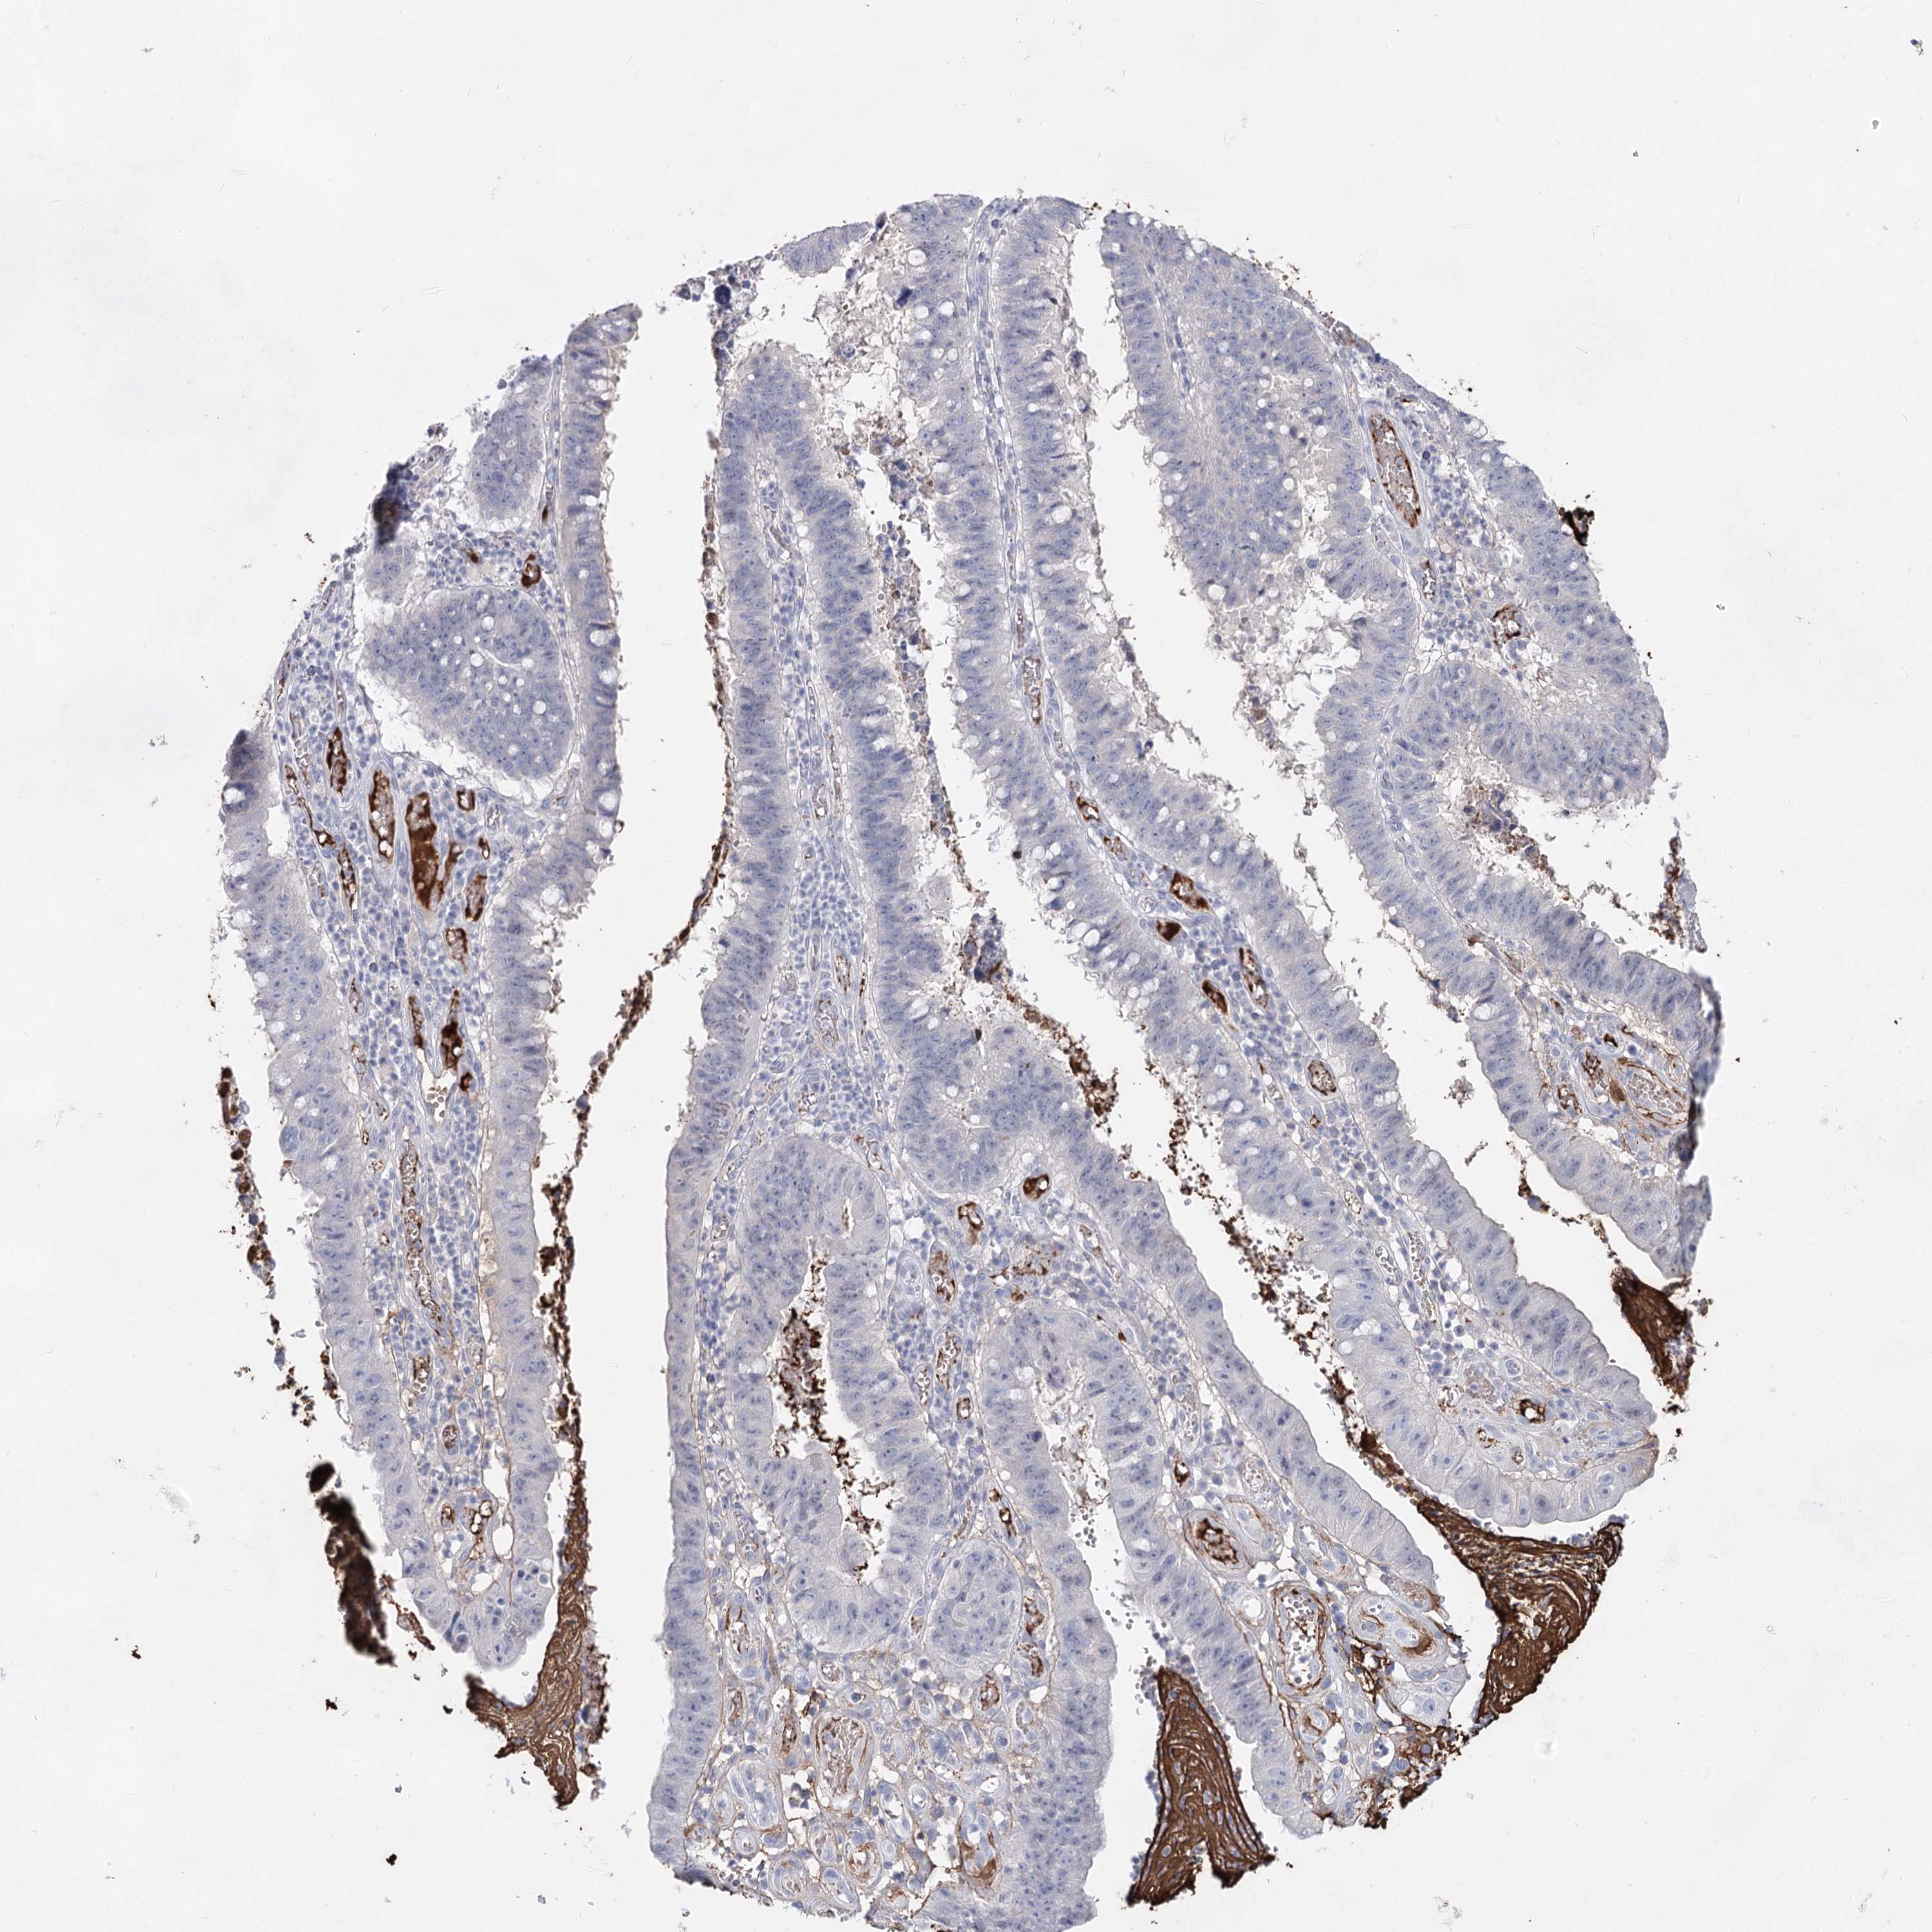

STOMACH CANCER - Protein expressioni

A mouse-over function shows sample information and annotation data. Click on an image to view it in a full screen mode. Samples can be filtered based on level of antibody staining by selecting one or several of the following categories: high, medium, low and not detected. The assay and annotation is described here.

Antibody stainingi

Antibody staining in the annotated cell types in the current human tissue is reported as not detected, low, medium, or high, based on conventional immunohistochemistry profiling in selected tissues. This score is based on the combination of the staining intensity and fraction of stained cells.

Each image is clickable and will lead to virtual microscopy that enables deeper exploration of all samples and also displays staining intensity scores, fraction scores and subcellular localization as well as patient and tissue information for each sample.

Antibody HPA038042

Antibody HPA038043

Staining

High

Medium

Low

Not detected

Intensity

Strong

Moderate

Weak

Negative

Quantity

>75%

75%-25%

<25%

None

Location

Nuclear

Cytoplasmic/membranous

Cytoplasmic/membranous,nuclear

Adenocarcinoma, NOS

Adenocarcinoma, High grade